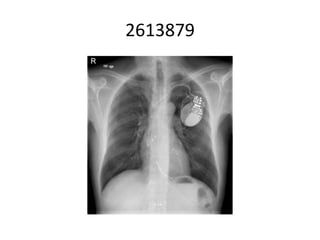

This document appears to be a medical record discussing Holter monitoring. It mentions reading and interpreting Holter data and includes the name of a doctor, date, and some medical abbreviations. However, there is not enough contextual information to provide a more detailed summary.